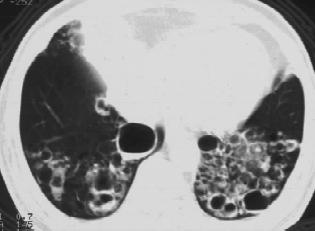

支气管扩张典型表现见图2-2和图2-3。

图2-2 双下肺支气管壁增厚,囊状扩张